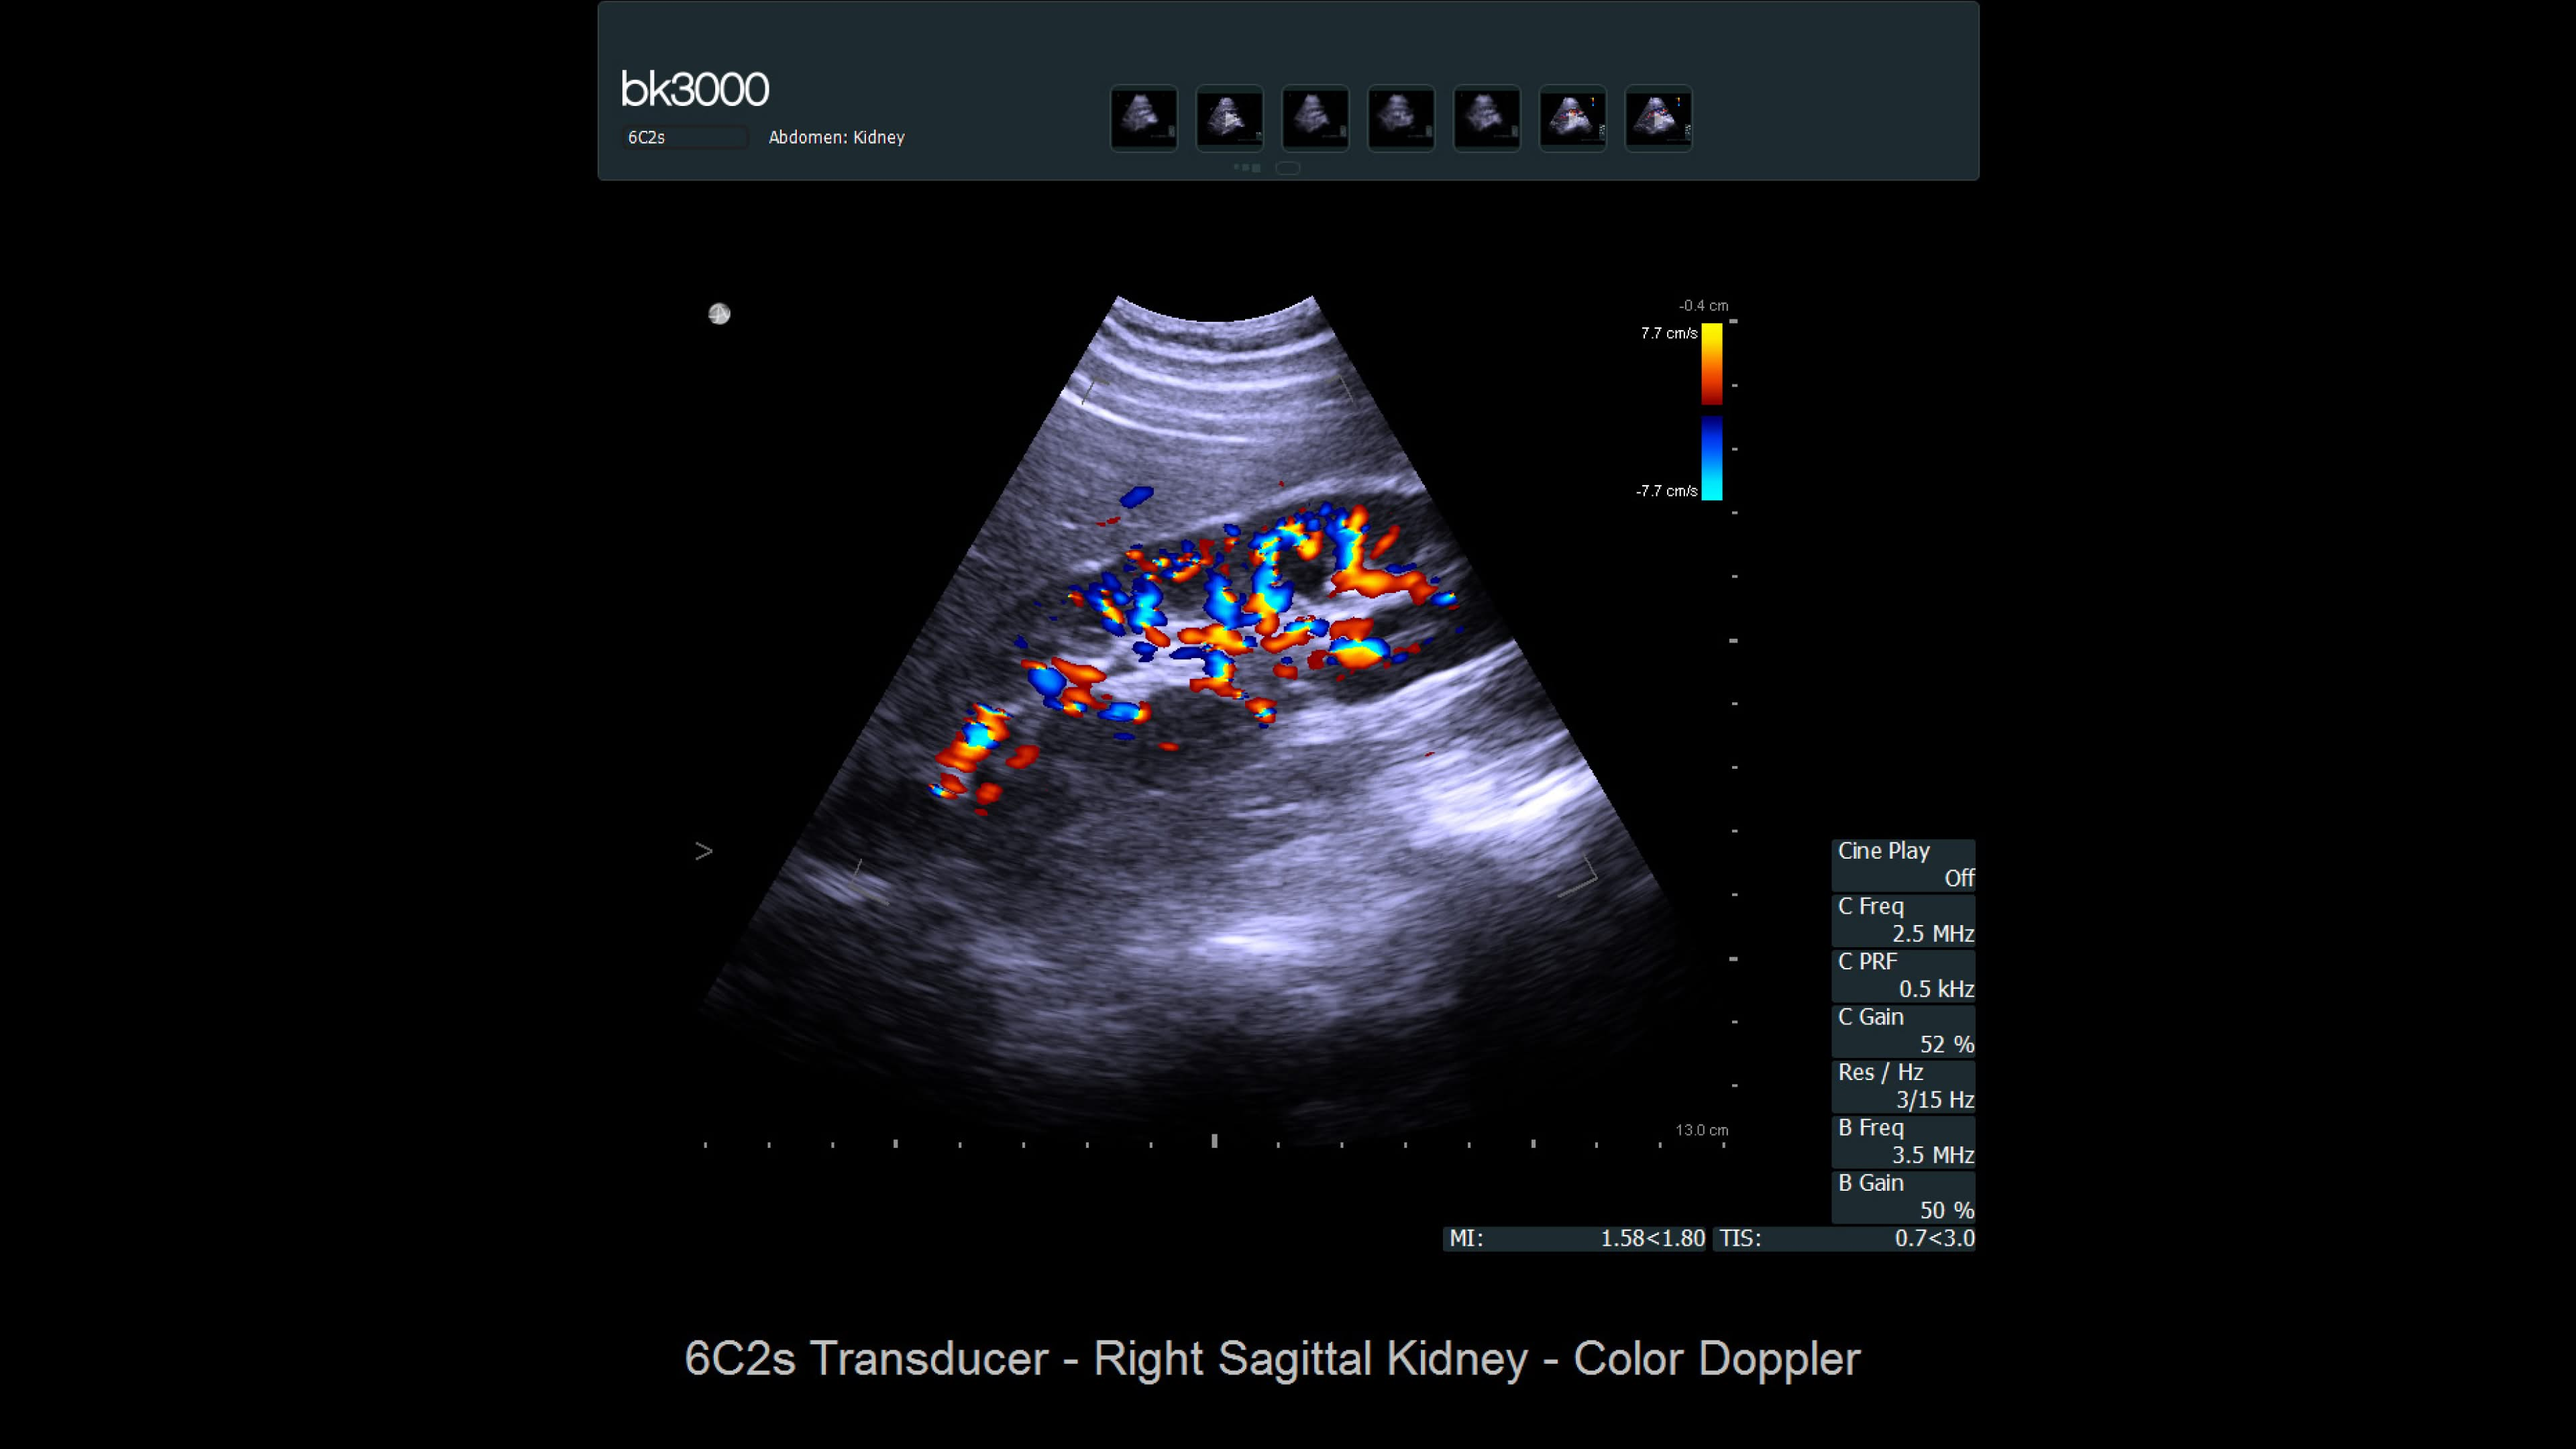

Kidney

Comprehensive kidney imaging solutions

Ultrasound provides detailed information for kidney imaging, measurement, and biopsies. The bk3000 and bkSpecto systems help visualize fine anatomical details, see vascularization, measure blood flow, and locate kidney stones. The bkActiv, our flagship system, offers next-level imaging for prostate, renal, kidney, and bladder imaging, with sensitive Doppler for blood flow. Combined with sterilizable transducers, the bkActiv sets a new standard for surgical urology.